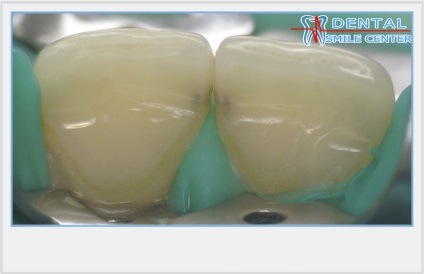

Modellezés fűrésszel vágott érintkező felületek.

Az eredeti eljárás ugyanazt a gyors, de biztonságos helyreállítás találkozott minket a mester osztályt a művészet helyreállítása az elülső fogak a bemutató Jeff Blank egy szimpóziumon évente megrendezett „Dentspy” az amerikai fogorvosok. Először szilikon minta helyreállítása az összes felső elülső fogak modellezett alapvetően palatális felülete és egy vágóéllel sarkok. Gumi gát hiányzik vagy mátrix vagy ékek, mint „gyilkos adhéziós” nem vonatkozik. Ezután az összes vágó részét egymást követően letétbe réteg dentin, zománc és világos színárnyalat modellezésével trowels vesztibuláris felületeket átmenetet az érintkező felületek. Végén a fogak már elválasztott egy fémes csiszoló szalag, amely a középső része a nem abrazív volt valami hasonlít egy fémfűrész. Modellezése érintkező felületek teljes befejező csíkok különböző súrlódástól.